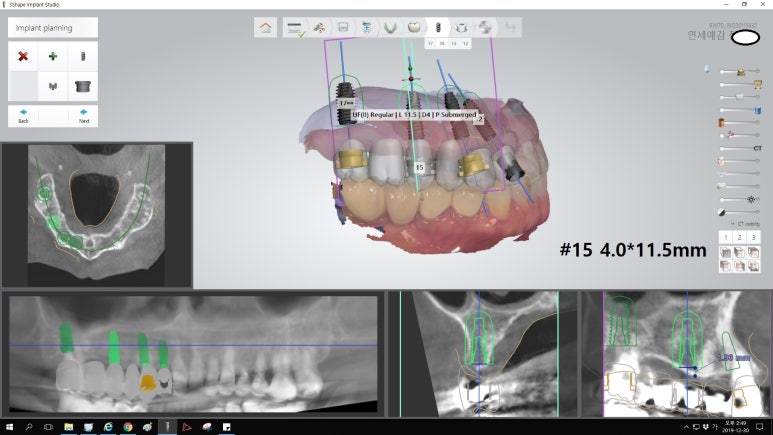

아래는 실제 저희 연세예감치과에서 내비게이션 인플란트를 시술한 환자분들의 모의시술 사진입니다.

빨간 색은 하악에 있는 큰 신경관으로 이 신경관을 건드릴 경우 감각 이상 등이 올 수 있어 이 신경관을 건드리지 않고 수술하도록 디자인되었습니다.